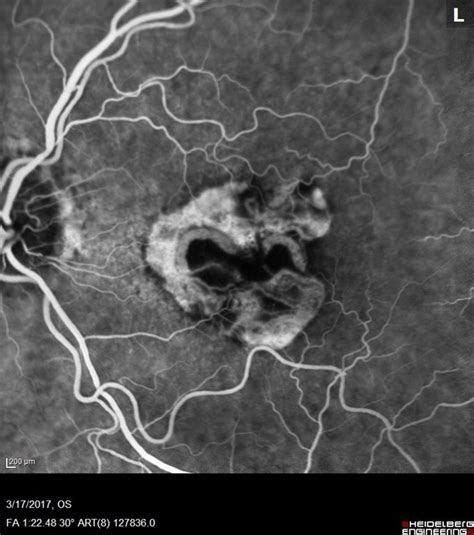

Another crucial test is the Fluorescein Angiography (FA) . In this procedure, a special dye called fluorescein is injected into a vein in your arm. As the dye circulates through the blood vessels in your eyes, a special camera takes a series of photographs. This allows the doctor to visualize the blood flow in the retina and choroid. If there are abnormal, leaky blood vessels associated with CNV , they will